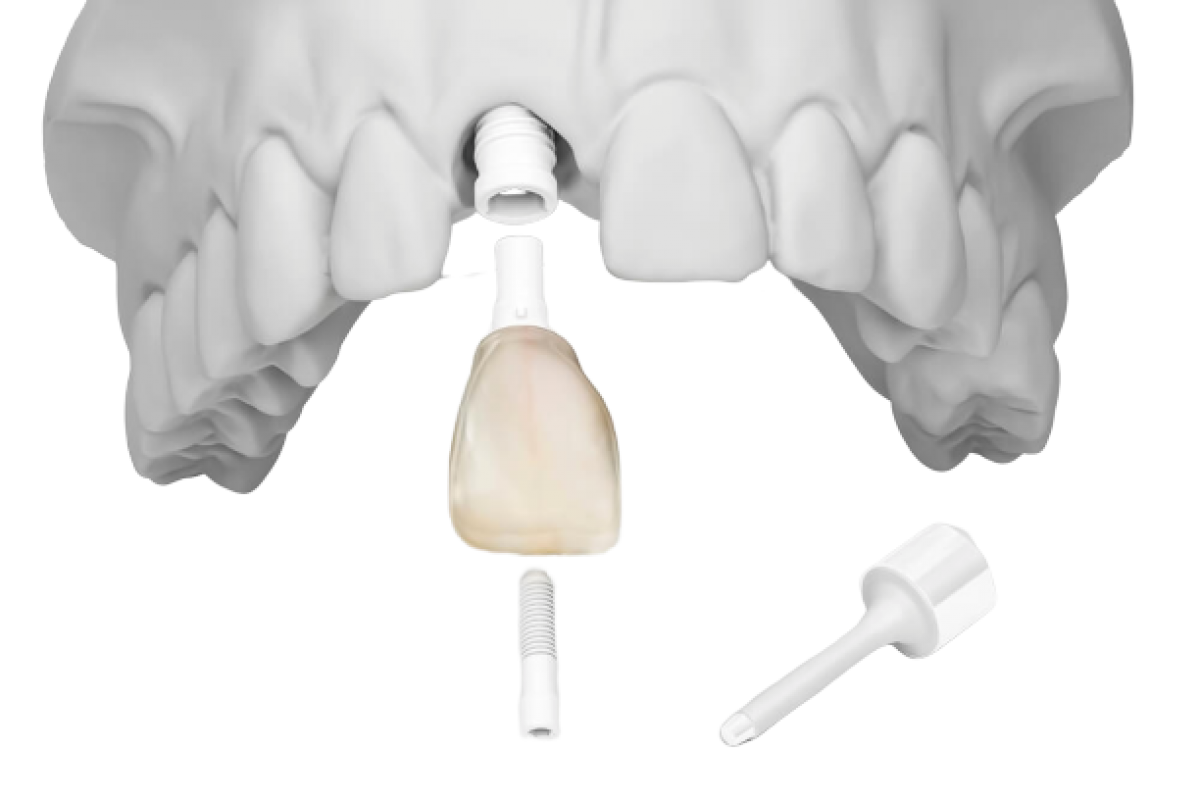

Современные коронки на зубные импланты: виды и фото-примеры